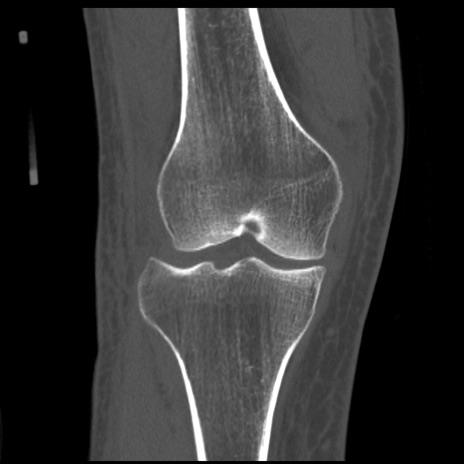

症例28 右膝関節CT(冠状断像)

右膝関節CT